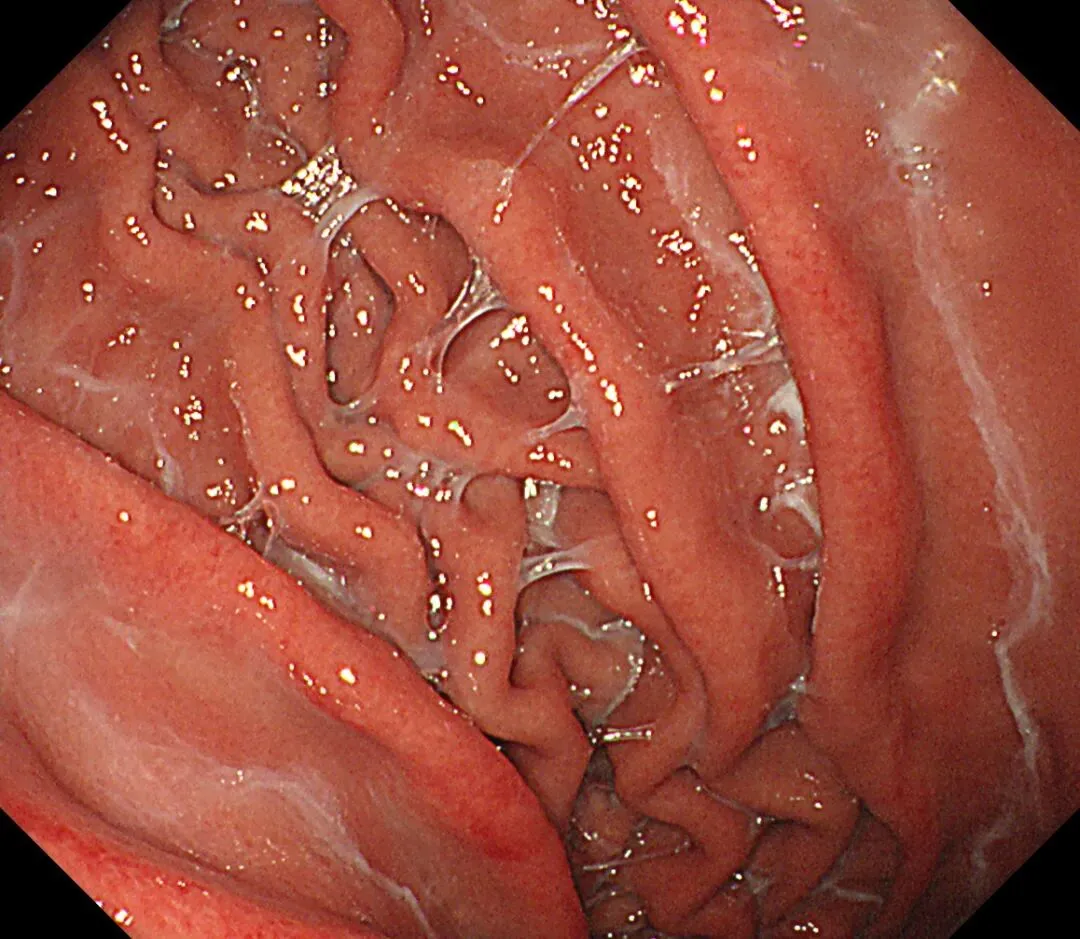

蛛网状黏液(web-like mucus):以胃底、胃体大弯为中心,有时可见白色透明、水洗难以去除的黏液附着,因外观与蜘蛛网相似而命名,多见于口服钾离子竞争性酸阻滞剂(P-CAB)患者,可能是因为其强效、持续抑酸作用所致,具体机制尚需进一步研究明确。

蛛网状黏液case1,服用P-CAB药物(具体服用时长不详)👇